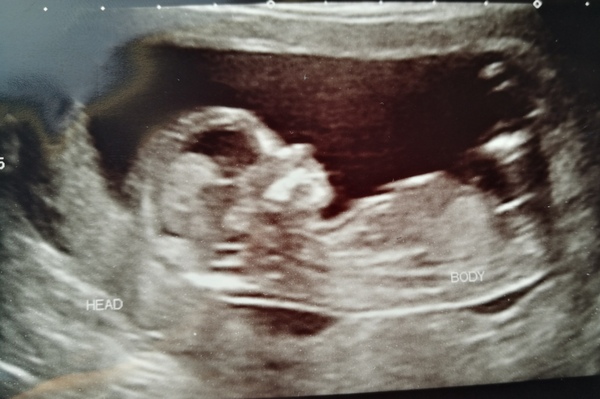

Beanmama18 · 09/03/2018 23:57

This is ours. I can let you all know on Monday what we're having :)

Beanmama18 · 10/03/2018 00:00

@Beanmama18 I'll guess girl

@Beanmama18 I’d also guess girl, if her little butt was led down straight your nub would be straight and not risen x

@Beanmama18 and @TheSleeperandTheSpindle I think both girls! However I am completely unqualified! You'll have to update on here when/if you know so we can see if we were right Grin